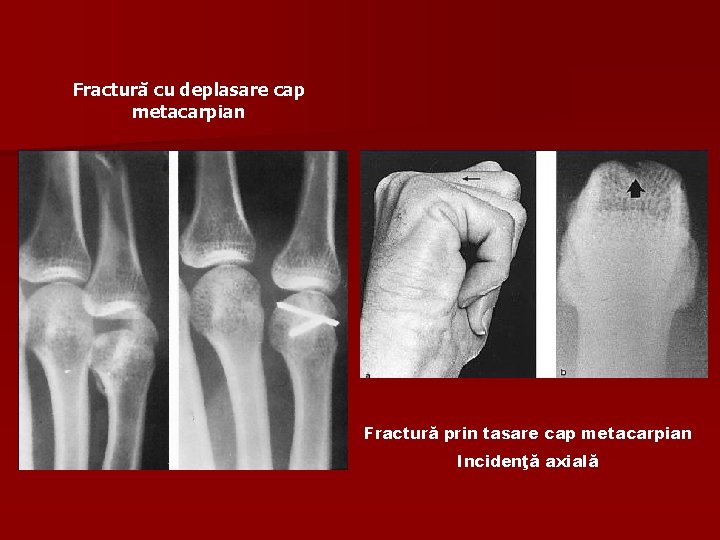

Fractură cu deplasare cap metacarpian Fractură prin tasare cap metacarpian Incidenţă axială